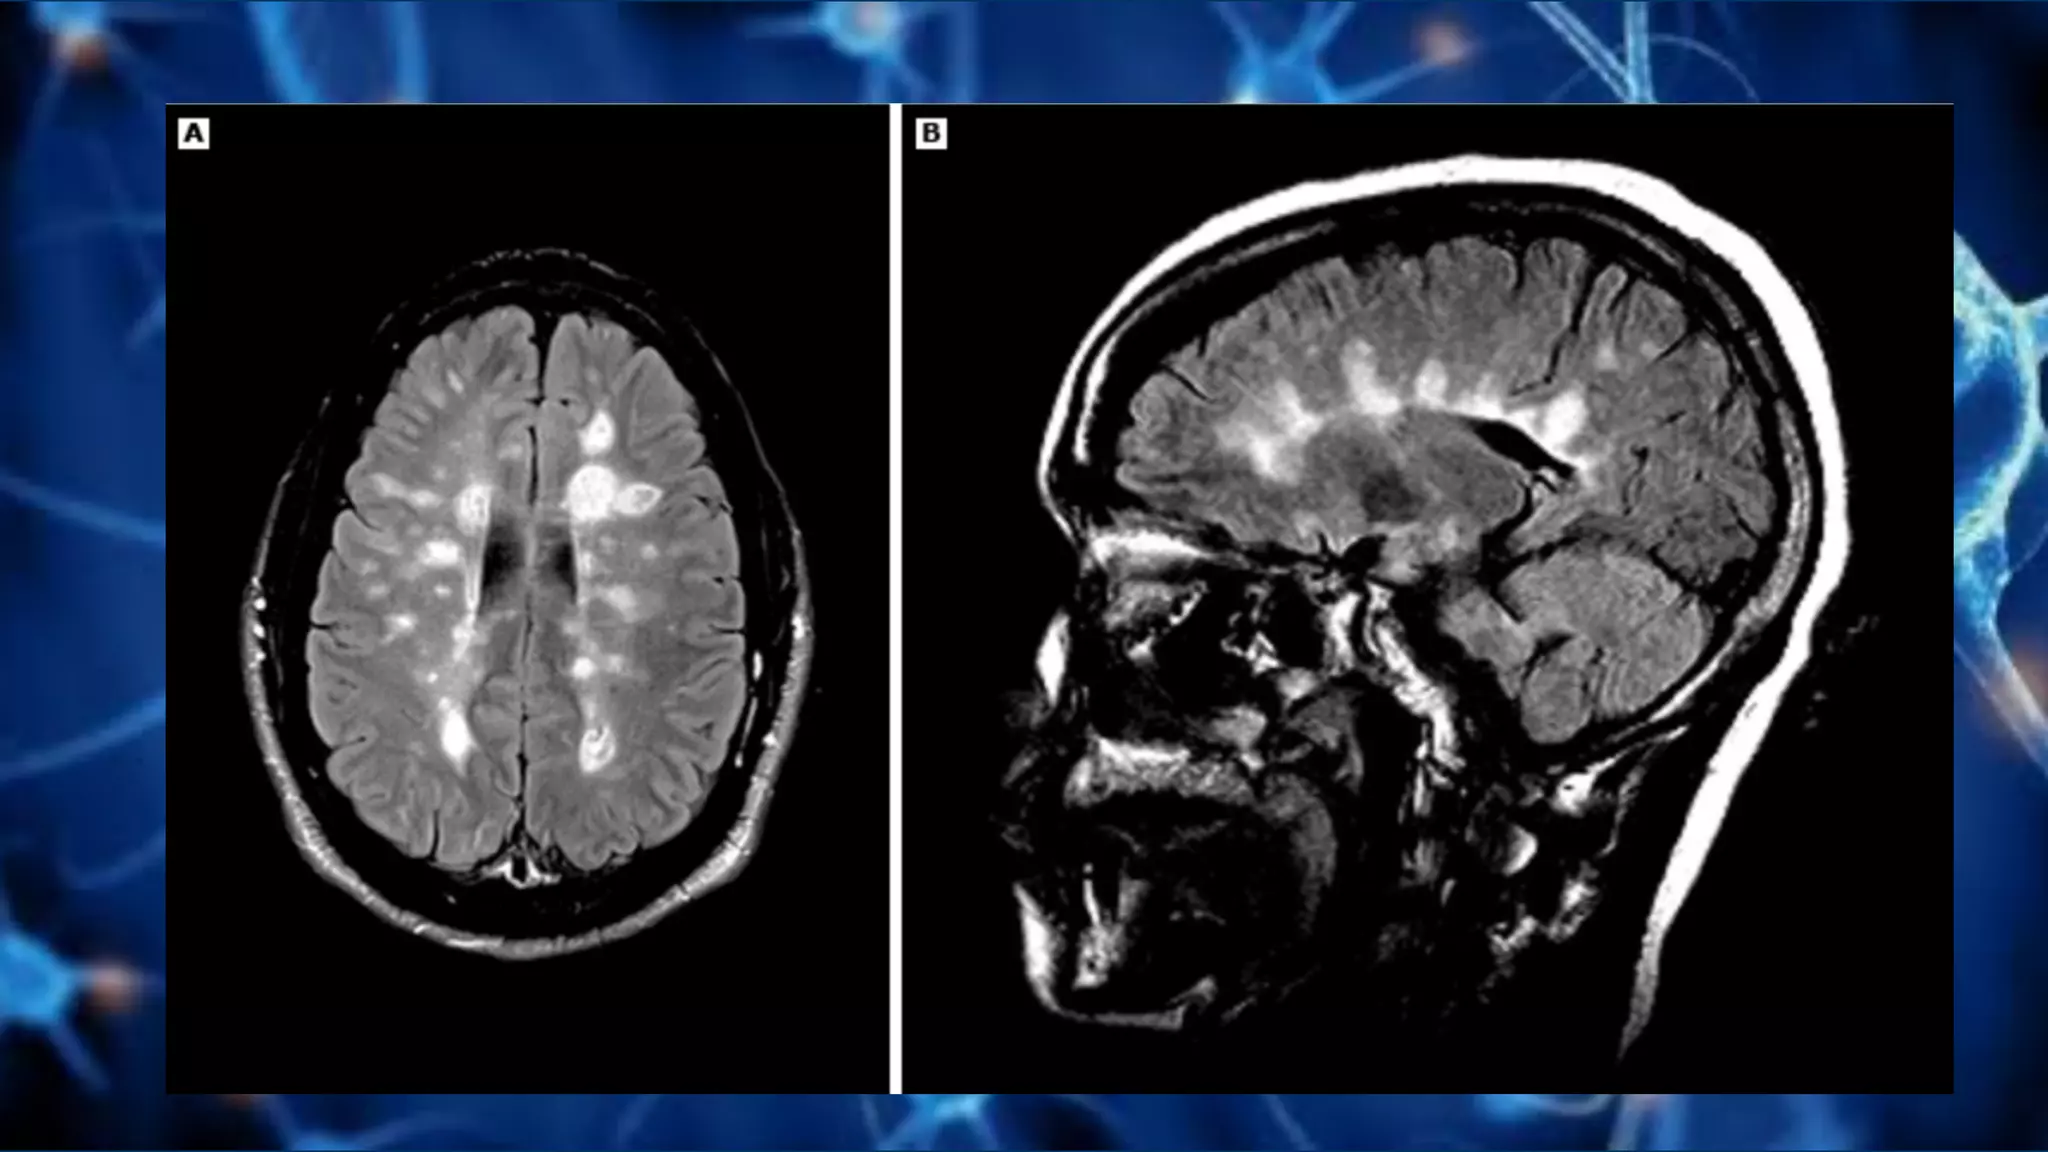

Lesiones activas vs crónicas

Gadolinio

• Aumenta intensidad de señal en T1

Agujeros negros

Pruebas auxiliares